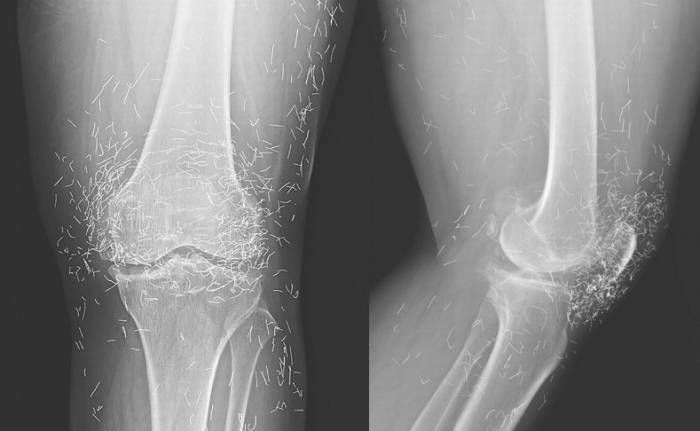

Μια 65χρονη γυναίκα από τη Νότια Κορέα υπέφερε από αρθρίτιδα και πήγε να κάνει μια σειρά ακτινογραφιών, στα πλαίσια παρακολούθησης της ασθένειάς της.

Το παράξενο είναι πως οι γιατροί, εκτός από τα εμφανή σημάδια της αρθρίτιδας, εντόπισαν ένα μεγάλο αριθμό από χρυσές βελονίτσες στα γόνατά της. Η γυναίκα είχε λάβει αγωγή με αναλγητικές ενέσεις και αντιφλεγμονώδη φάρμακα στο παρελθόν, ωστόσο οι πόνοι δεν υποχωρούσαν.

Επιπλέον, οι θεραπείες που της είχαν προταθεί της προκαλούσαν γαστροεντερικές ενοχλήσεις. Συνεπώς, κατέφυγε στην πανάρχαια μέθοδο του βελονισμού ως μέσου αντιμετώπισης του πόνου. Η συγκεκριμένη εκδοχή της θεραπείας αυτής, περιλαμβάνει τη μόνιμη εισαγωγή χρυσών βελόνων στο σώμα του ασθενούς.

Η γυναίκα πήγαινε στο βελονιστή μια φορά τη βδομάδα και ως αποτέλεσμα συσσ��ρεύτηκε στο σώμα της μια πληθώρα από χρυσές βελόνες. Σύμφωνα με τους γιατρούς, το σκεπτικό πίσω από την τεχνική αυτή είναι το εξής: οι χρυσές βελόνες που τοποθετούνται μόνιμα στο σώμα του υπό θεραπεία ατόμου, επενεργούν ως μόνιμος βελονισμός και η χρήση αυτή στην αντιμετώπιση της οστεοαρθρίτιδας και της ρευματοειδούς αρθρίτιδας είναι εξαιρετικά διαδεδομένη στις ασιατικές χώρες.